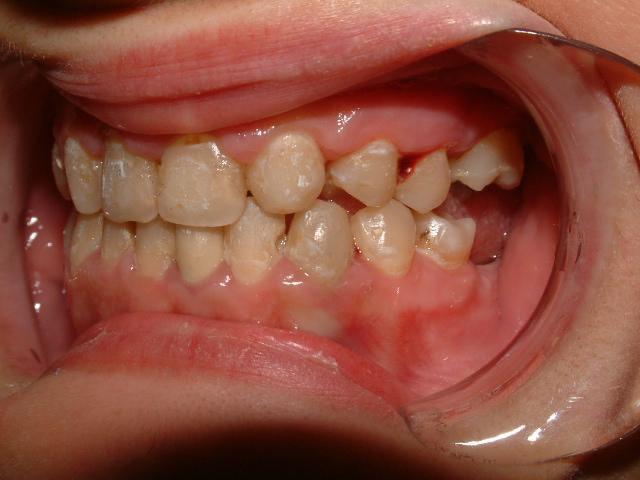

1η περίπτωση

Αρχική οδοντοσκελετική κατάσταση παιδιού με προγναθισμό άνω γνάθου και έντονη οριζόντια πρόταξη άνω τομέων Η σημασία της στοματικής υγιεινής και ορθοδοντικής

026

πρόληψης

027 Αμέσως μετά το τέλος της ορθοδοντικής θεραπείας. Οι αλλαγές στην οδοντική του σύγκλειση αλλά και στο πρόσωπο είναι εμφανείς 15 χρόνια μετά την αρχική περάτωση της θεραπείας, το αποτέλεσμα παραμένει σταθερό και ο ασθενής απέκτησε ένα υγιές και αρμονικό χαμόγελο και πρόσωπο. Η σημασία της στοματικής υγιεινής και ορθοδοντικής πρόληψης

028 Δεύτερη περίπτωση Αρχική κατάσταση Η σημασία της στοματικής υγιεινής και ορθοδοντικής πρόληψης

Μετά το πέρας της ορθοδοντικής θεραπείας.